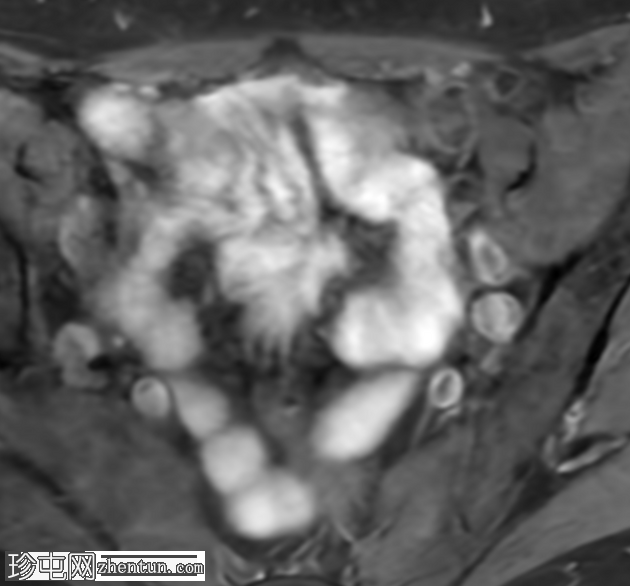

轴位T2加权像

脂肪抑制像

盆腔MRI显示右侧卵巢解剖位置可见一边界清晰的卵圆形肿块。该病灶由囊性和实性成分组成。囊性部分壁薄,在T2加权像上呈均匀高信号,在T1加权脂肪抑制序列上呈低信号,无对比剂增强。该实性成分的信号特征与正常卵巢组织相似,DWI成像未见扩散受限,静脉注射造影剂后未见异常强化。

此外,在子宫左侧壁可见一管状薄壁囊性结构,延伸至同侧髂外血管,末端呈盲端。该结构在T2加权像上呈均匀高信号,在T1加权脂肪抑制序列上呈低信号,且无造影剂强化。

本例中,盆腔MRI显示,患者右侧卵巢解剖位置存在一个边界清晰的附件肿块,该患者有20年前行双侧输卵管卵巢切除术的病史。该病灶包含囊性和实性成分,其中实性部分表现出与正常卵巢组织相似的信号特征。无扩散受限和无可疑的增强扫描强化提示排除恶性病变。这些影像学特征结合相关的手术史进行解读,符合残留卵巢组织的特征,支持卵巢残留综合征的诊断。此外,还发现对侧子宫左侧延伸出一个管状薄壁囊性结构,末端呈盲端。其形态、信号特征和无强化表现符合输卵管残端或输卵管残端积水,这是输卵管切除术后常见的术后表现。附件残余的存在进一步支持术后病因,而非原发性妇科肿瘤

主要鉴别诊断包括腹膜包涵囊肿、子宫内膜异位症相关囊肿和附件肿瘤。腹膜包涵囊肿通常位于腹膜腔内,不含类似卵巢组织的实性成分。子宫内膜异位囊肿通常在T1加权像上表现为高信号,T2加权像上出现阴影,并具有其他特征性MRI表现,而本例4中均未见这些表现。鉴于无扩散受限、无可疑强化以及实性成分的良性影像学表现,肿瘤性病变的可能性较小。